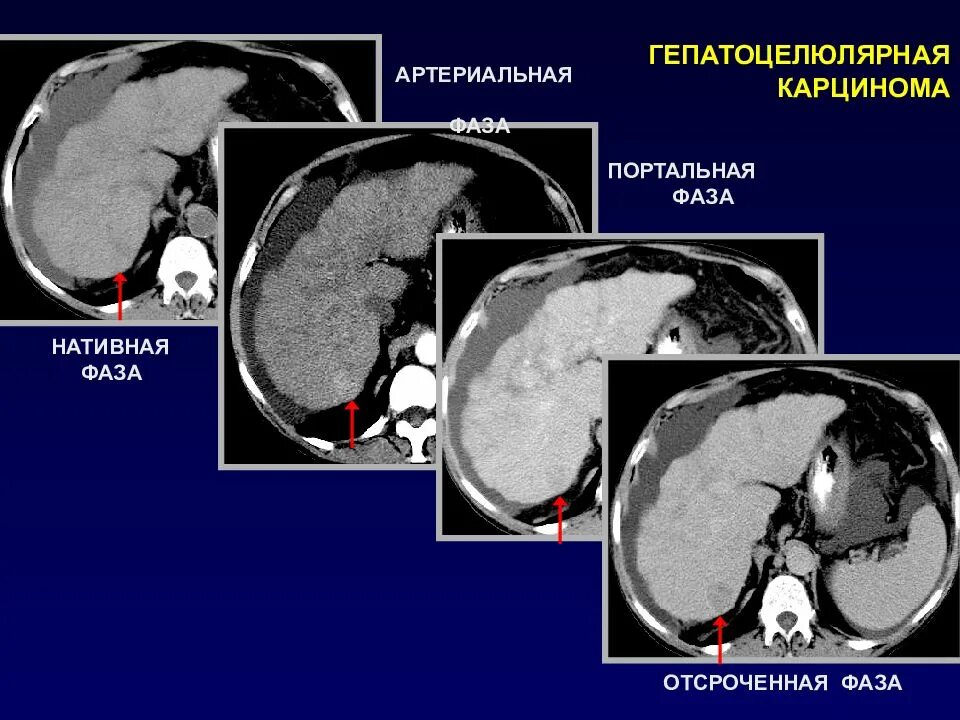

Фазы кт